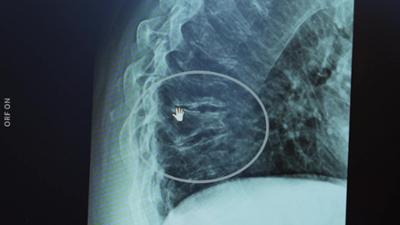

Bewusst gesund- Dialyse Neu: Schonender Gefäßzugang ohne Operation | Studiogespräch: Was kann interventionelle Radiologie? | "Bewusst gesund"-Tipp: Luft im Bauch | Sport gegen Schmerzen und Krankheiten | Banane im Faktencheck